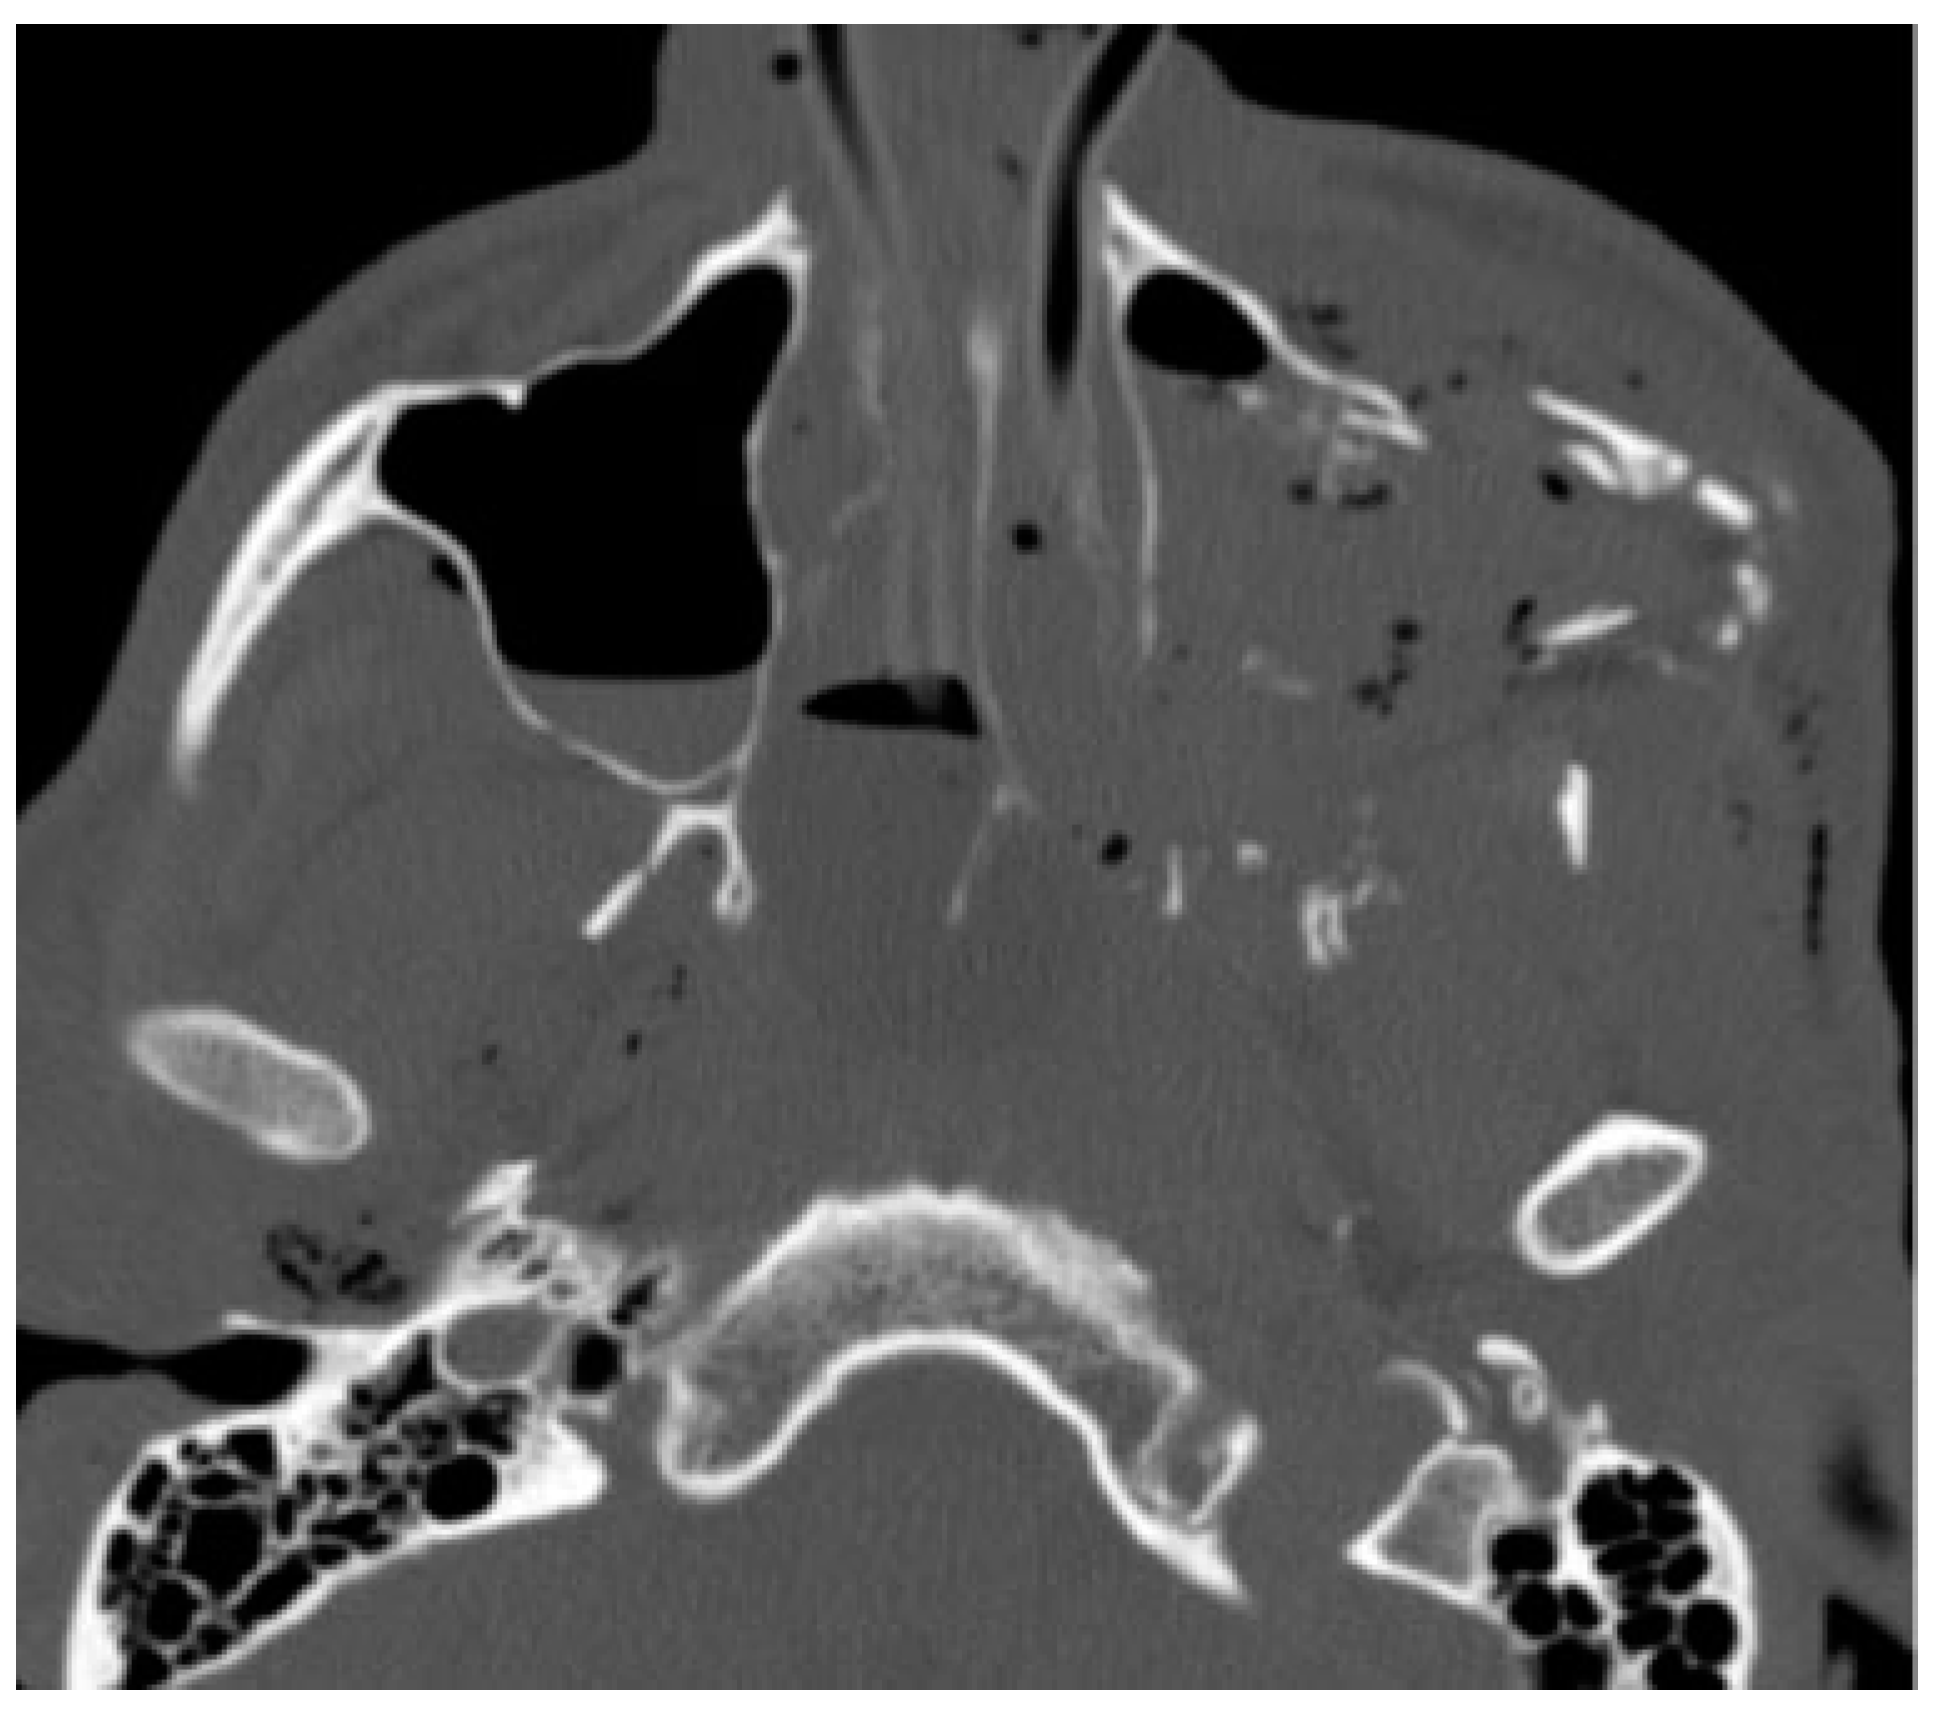

:Case Report